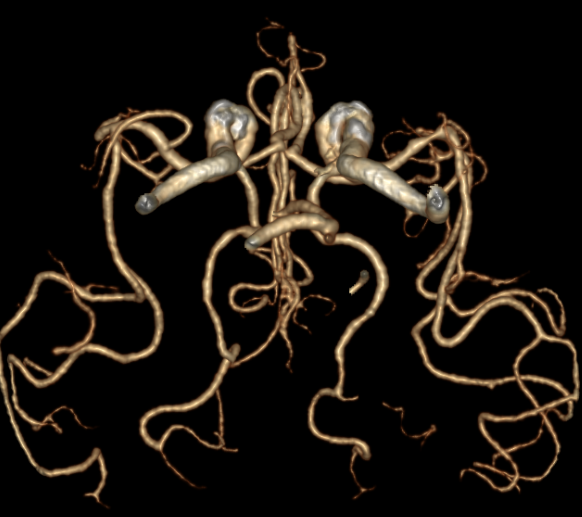

CTA提示右侧大脑中动脉M2段下干闭塞。

动脉长鞘怎么置入有励可说|Locaste 088励楷长鞘及Tarvos微导丝在右侧大脑中动脉M2段取栓术中的应用_https://www.jmylbn.com_新闻资讯_第6张